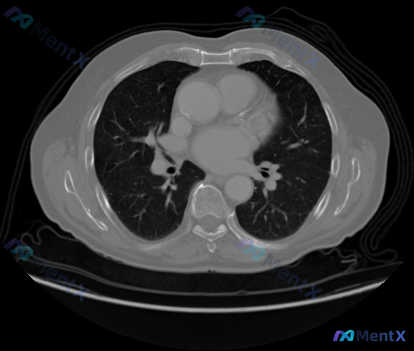

这是一张胸部CT纵隔窗横断面:

- 纵隔淋巴结:隆突下、双侧肺门、气管旁及主动脉弓周围,都没见明显肿大的淋巴结,间隙也很清晰。

- 大血管与心脏:心脏大血管形态、走行、管径都还好,没见心包积液,上腔静脉也没受压。

- 纵隔软组织与脂肪:前纵隔脂肪透亮度好,没见胸腺增大或异常肿块,也没见条索或渗出。

- 气道与可见肺实质:气管分叉角度正常,左右主支气管通畅,管壁光滑;虽然是纵隔窗,但能看到的肺门周围血管纹理走行自然,没见明确占位。